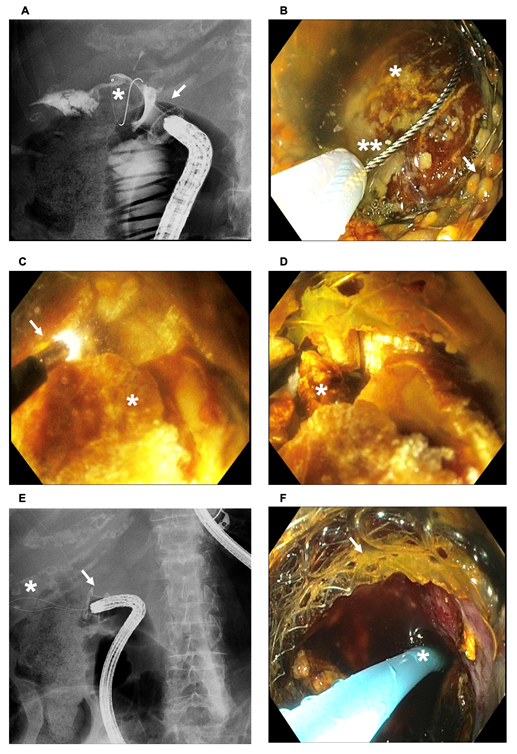

Four months later, upper right abdominal discomfort arose, accompanied by sepsis. Endoscopic ultrasound-guided fluoroscopy revealed a 20 mm bile stone obstructing the cholecysto-duodenostomy by LAMS, which led to early gangrenous cholecystitis. This prompted the endoscopic management by SpyGlass-guided electrohydraulic lithotripsy (SGEHL) of the macrolithiasis with the removal of stone debris. We present an image taken by fluoroscopy of the 20 mm bile stone lodged in the LAMS responsible for early gangrenous cholecystitis in our patient (Figure 2A). Figure 2B shows a Spyglass image of the obstructed 20 mm bile stone in the LAMS. We then proceeded with LAMS obstruction lithotripsy (LOL), involving the fragmentation of the lodged lithiasis using EHL through the LAMS (Figure 2C and Figure 2D). Figure 2E illustrates the passage of an endoscopic loop through the cholecysto-duodenostomy after elimination of the lodged bile stone and bile debris. A double-pigtail plastic biliary stent was placed through the unobstructed LAMS, as illustrated in Figure 2F.

Figure 2 (A) Image taken by fluoroscopy of the 20 mm bile stone lodged (asterisk) in the LAMS (arrow) responsible for early gangrenous cholecystitis in our patient; (B) Spyglass image of the obstructed 20 mm bile stone (asterisk) in the LAMS (arrow) and endoscopic loop (double asterisk); (C) LAMS obstruction electrohydraulic lithotripsy (arrow)(LOL) of the obstructive bile stone (asterisk) through the LAMS; (D) Fragmentation of the lodged lithiasis (asterisk); (E) Passage of an endoscopic loop (asterisk) through the cholecysto-duodenostomy (arrow) after elimination of the lodged bile stone and bile debris; (F) Placement of a double-pigtail plastic biliary stent (asterisk) through the unobstructed LAMS (arrow).